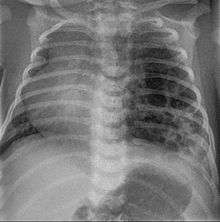

Congenital pulmonary airway malformation (CPAM), formerly known as congenital cystic adenomatoid malformation (CCAM), is a congenital disorder of the lung similar to bronchopulmonary sequestration. In CPAM, usually an entire lobe of lung is replaced by a non-working cystic piece of abnormal lung tissue. This abnormal tissue will never function as normal lung tissue. The underlying cause for CPAM is unknown. It occurs in approximately 1 in every 30,000 pregnancies.[1]

CPAMs are often identified during routine prenatal ultrasonography. Identifying characteristics on the sonogram include: an echogenic (bright) mass appearing in the chest of the fetus, displacement of the heart from its normal position, a flat or everted (pushed downward) diaphragm, or the absence of visible lung tissue.

CPAMs are classified into three different types based largely on their gross appearance. Type I has a large (>2 cm) multiloculated cysts. Type II has smaller uniform cysts. Type III is not grossly cystic, referred to as the "adenomatoid" type. Microscopically, the lesions are not true cysts, but communicate with the surrounding parenchyma. Some lesions have an abnormal connection to a blood vessel from an aorta and are referred to as "hybrid lesions."

Imaging

The earliest point at which a CPAM can be detected is by prenatal ultrasound. The classic description is of an echogenic lung mass that gradually disappears over subsequent ultrasounds. The disappearance is due to the malformation becoming filled with fluid over the course of the gestation, allowing the ultrasound waves to penetrate it more easily and rendering it invisible on sonographic imaging. When a CPAM is rapidly growing, either solid or with a dominant cyst, they have a higher incidence of developing venous outflow obstruction, cardiac failure and ultimately hydrops fetalis. If hydrops is not present, the fetus has a 95% chance of survival. When hydrops is present, risk of fetal demise is much greater without in utero surgery to correct the pathophysiology. The greatest period of growth is during the end of the second trimester, between 20–26 weeks.